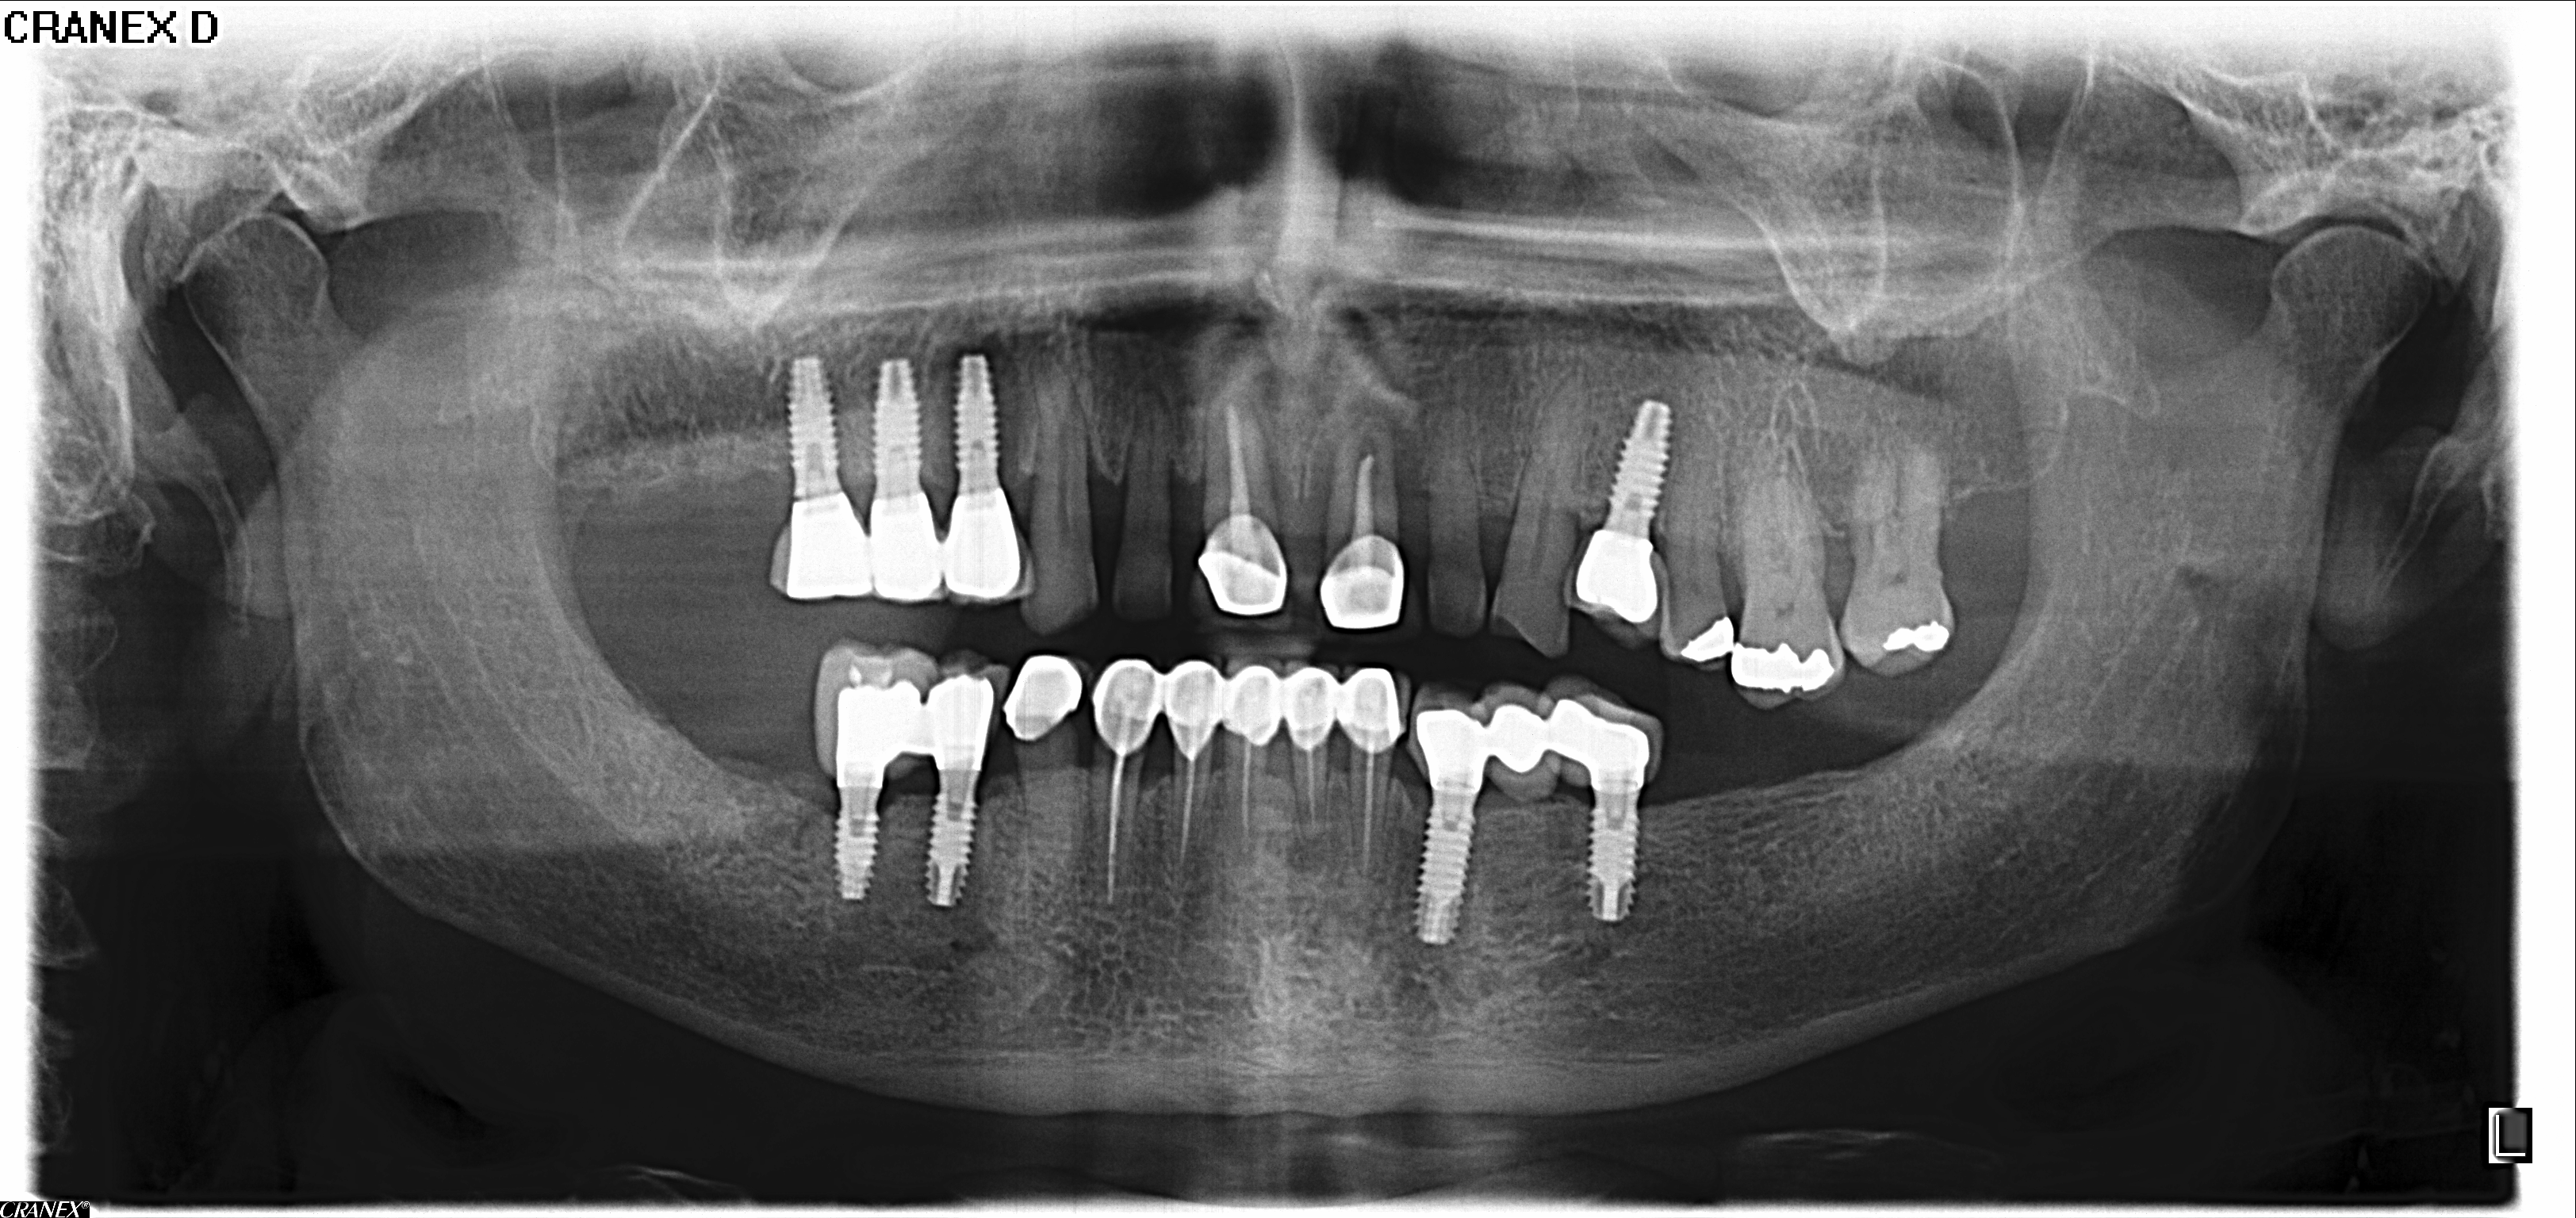

Cuando acabé con los “problemas del brazo izquierdo” empecé con las consultas “odontológicas” que también me han retenido en Madrid unos días. Pensé de inicio que lo llevaba mal porque tenía un diente que no tenía mucho futuro y acabé teniendo que pedir varios presupuestos por que el primero ascendía a millón y medio de pesetas y yo ciertamente no soy pudiente.

Radiografía antes del último proceso.

Elegida la nueva clínica dental acabaron sacándome cuatro piezas y para compensar me pusieron cuatro nuevos tornillos, no os cuento como quedó la boca y sobre todo las ganas de viajar. Acotados los problemas médicos que a los “viejos” nos condicionan la vida pensé en volver a la carretera, pero no, resulta que al inquilino que tenía en la casa familiar de Valladolid le despidieron de la “supuesta” nueva fábrica de autobuses eléctricos de Valladolid y tengo que volverme a ocupar de esa minucia que para mí es como si tuviera que escalar el K2 sin cuerdas , sherpas, ni oxígeno.